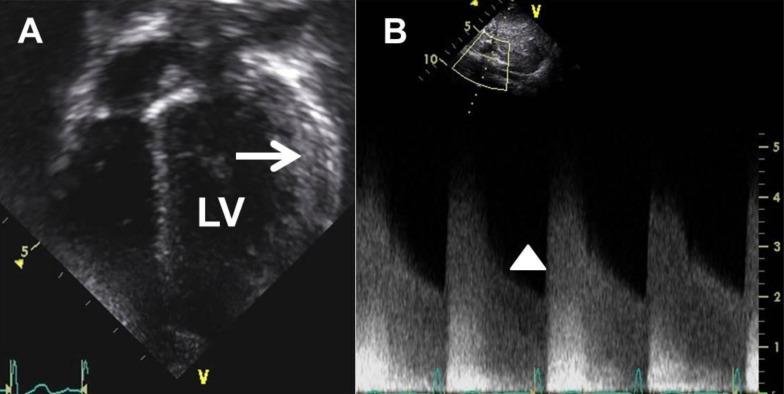

Midaortic syndrome (MAS) is a rare vascular disease that commonly causes renovascular hypertension. The lumen of the abdominal aorta narrows and the ostia of the branches show stenosis. MAS is associated with diminished pulses in the lower extremities compared with the upper extremities, severe hypertension with higher blood pressure in the upper rather than lower extremities, and an abdominal bruit. The clinical symptoms are variable, and recognition in children with hypertension can aid early diagnosis and optimal treatment. Hypertension with MAS is malignant and often refractory to several antihypertensive drugs. Recently, radiologic modalities have been developed and have led to numerous interventional procedures. We describe the case of a 3-year-old boy presenting with left ventricular hypertrophy whose severely elevated blood pressure led to the diagnosis of idiopathic MAS. This case highlights the importance of measuring blood pressure and conducting a detailed physical examination to diagnose MAS. This is the first reported case of idiopathic MAS diagnosed in childhood in Korea.

中段主动脉综合征(MAS)是一种罕见的血管疾病,通常会导致肾血管性高血压。腹主动脉管腔变窄,分支开口处出现狭窄。与上肢相比,MAS与下肢脉搏减弱、上肢血压高于下肢的严重高血压以及腹部杂音有关。临床症状多变,对高血压儿童的识别有助于早期诊断和最佳治疗。MAS所致高血压为恶性,通常对多种降压药物耐药。近年来,影像学技术不断发展,催生了众多介入治疗手段。我们描述了一名3岁男孩的病例,该男孩因左心室肥厚就诊,其严重升高的血压最终导致特发性MAS的诊断。该病例突出了测量血压和进行详细体格检查对诊断MAS的重要性。这是韩国首例报道的儿童期诊断的特发性MAS病例。